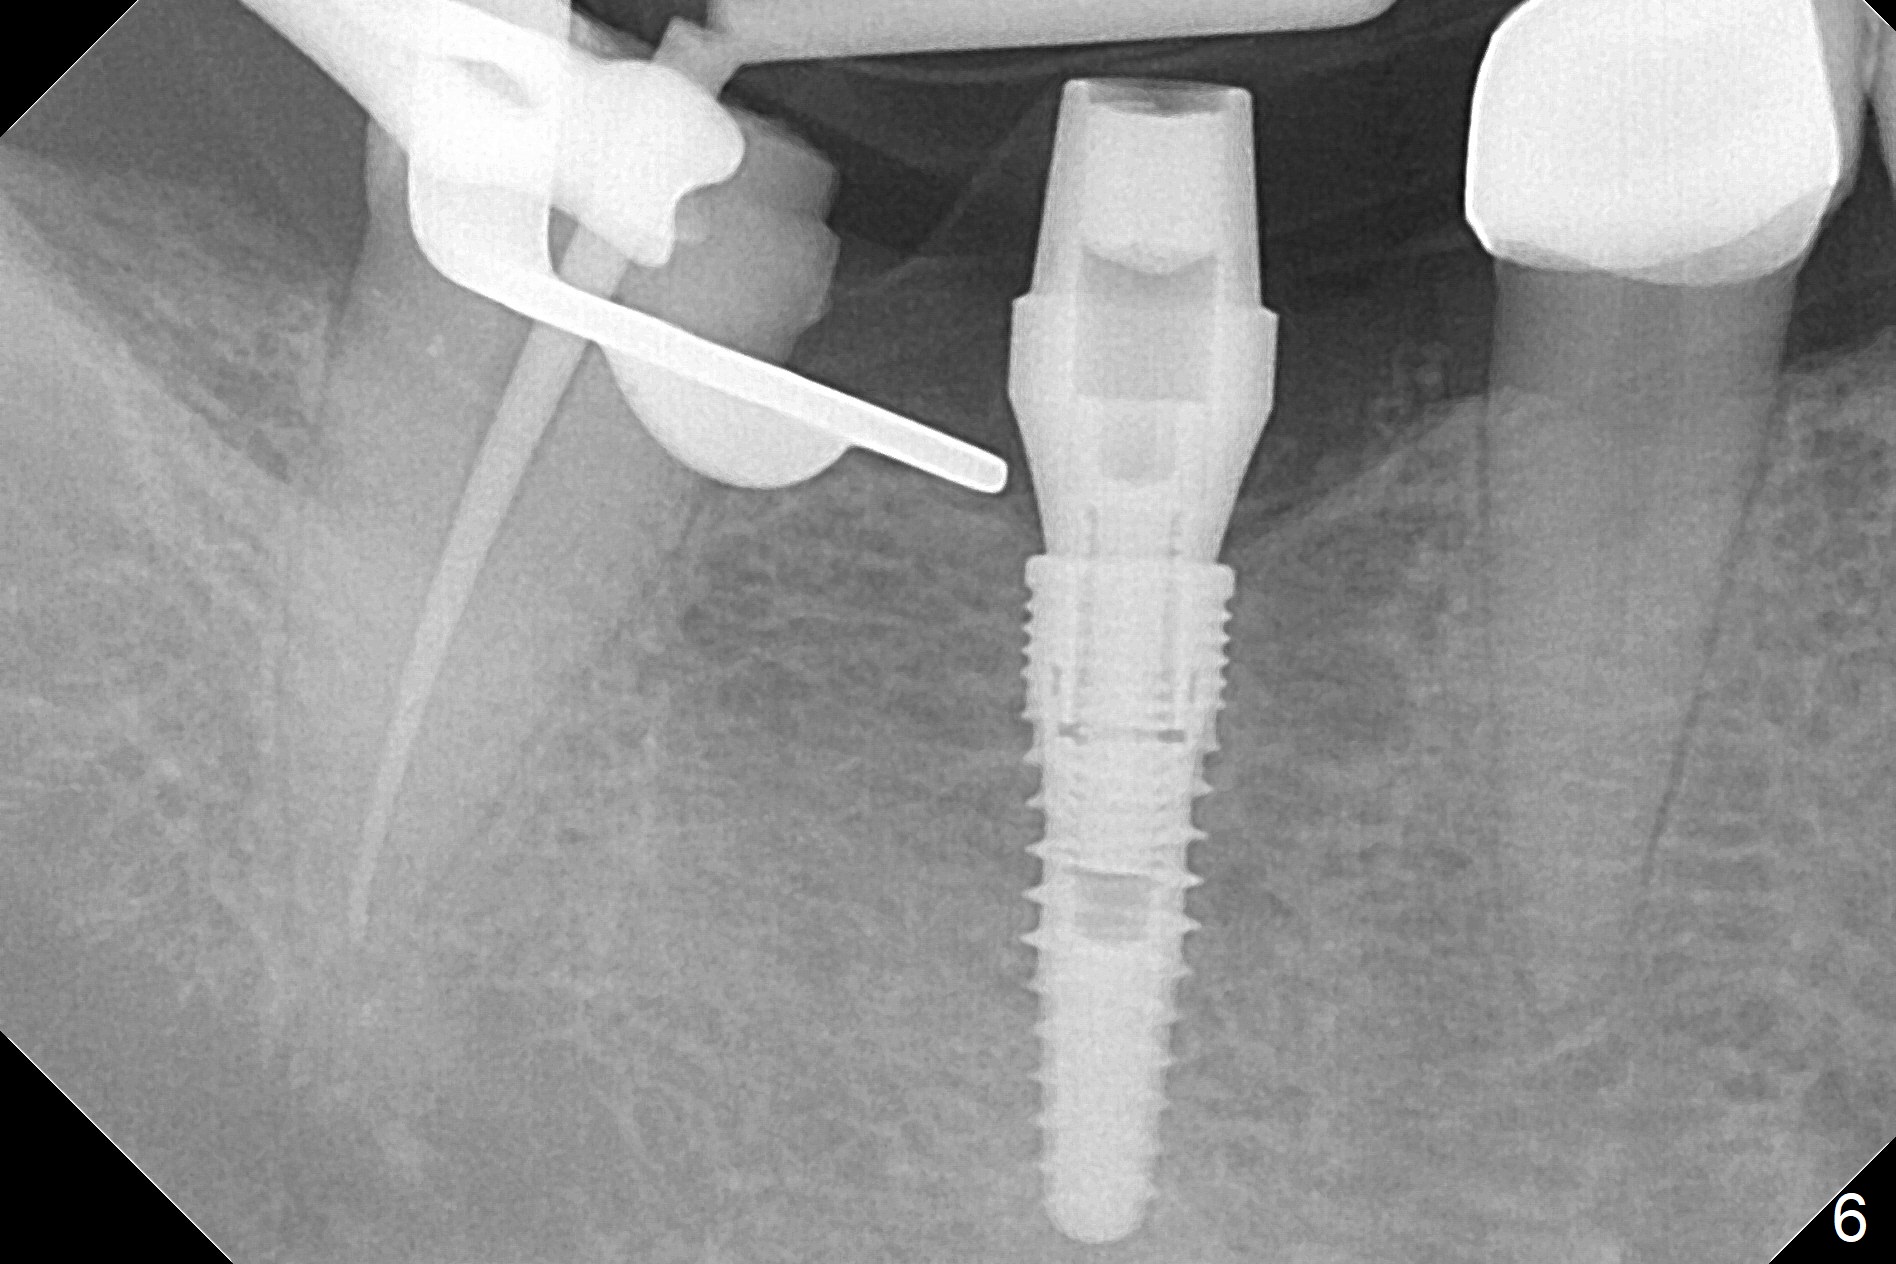

The apparently narrow ridge at #30 before bridge sectioning (Fig.1) is confirmed with incision (Fig.2). Following ridge reduction, osteotomy is initiated with 2 mm pilot drill (Fig.3). When a 3.8x12 mm SM narrow implant is placed with 40 Ncm, there is 1-2 mm cortical bone buccolingually (Fig.4,5). The thick cortices do not seem to be easy to be bent, i.e., expanded. RCT is finished at #31 one month post implant placement (Fig.6,7), the flattened ridge appears to have started to undergo remodeling. Ridge reduction makes it possible for the implant to remain subcrestal postop (Fig.4). The bone surrounding the implant may reduce the likelihood of implant fracture. The crowns at #30 and 31will be fabricated together with light occlusion at #30. In fact the splinted provisional dislodges. There appears dense bone formation 3 months postop (Fig.8 *). The drawback of using a SM narrow implant is that a narrow abutment has to be used (4.8x4(4.5) mm). The implant crown is dislodged immediately after the patient finishes lunch. Following recementation, the occlusion is reduced. In fact, UF or IBS has no such drawback: the implant could be small, but the abutment could be large. One year post cementation, the crown at #31 needs recementation (Fig.9); the bone density next to the coronal implant increases (*).